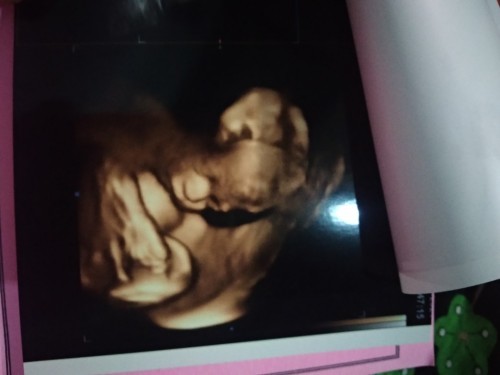

Bun saya mau tanya? Saya sudah 7bulan kok pergerakan bayi nya kurang bergerak atau kurang lincah ya?

Saya baru hamil pertama Bun?